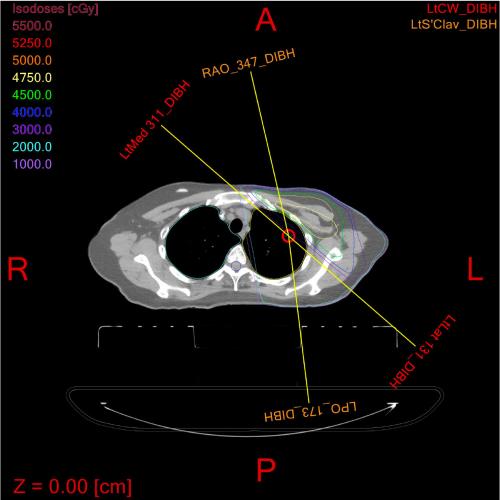

Image

Medical x-ray showing bone with two linked black gaps.